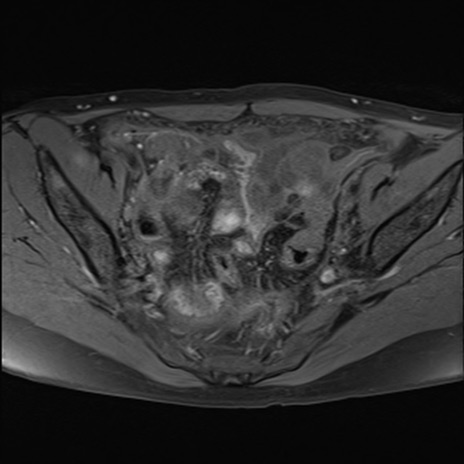

症例39 脂肪抑制T1WI(横断像)

MRI(4日後)

T2WI(横断像)